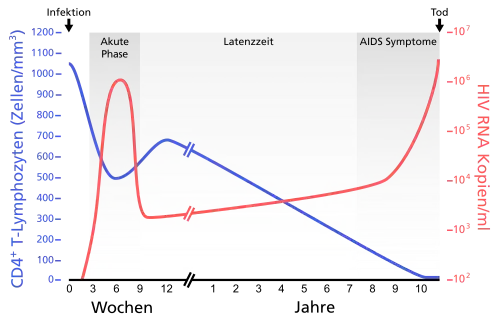

Verlauf der HIV-Infektion

Eine unbehandelte HIV-Infektion verläuft in der Regel in mehreren Stadien. Nach einer Inkubationszeit von etwa drei bis sechs Wochen kommt es nach der Ansteckung meist zu einer akuten HIV-Infektion. Dieses akute Initialstadium ist unter anderem durch Fieber, Nachtschweiß,[102] Abgeschlagenheit, Hautausschläge (makulöses Exanthem), orale Ulzerationen oder Arthralgie (Gelenkschmerzen) und Kopfschmerzen[103] gekennzeichnet. Wegen der Ähnlichkeit mit grippalen Infektionen bleibt die akute HIV-Infektion meistens unerkannt. Eine frühe Diagnose ist jedoch wichtig: Durch sie können nicht nur weitere Infektionen von Sexualpartnern verhindert werden. Erste Studien an Patienten, die während der akuten HIV-Infektion antiviral behandelt wurden und nach einiger Zeit die Therapie absetzten, zeigten, dass die HIV-spezifische Immunantwort der Patienten gestärkt werden konnte.[104][105] Die akute Infektion dauert selten mehr als vier Wochen an.

In der folgenden meist mehrjährigen Latenzphase treten keine gravierenden körperlichen Symptome auf. Veränderte Blutwerte und eine schleichende Lipodystrophie bleiben von den HIV-Infizierten oftmals unbemerkt. Danach kommt es vielfach zu ersten Erkrankungen, die auf ein mittelschwer geschwächtes Immunsystem zurückzuführen sind, jedoch noch nicht als AIDS-definierend gelten (CDC Klassifikation B, siehe AIDS).

Zerstörung von CD4-Helferzellen

Im Verlauf einer HIV-Infektion werden unter anderem CD4+-Helferzellen kontinuierlich auf verschiedenen Wegen zerstört, was eine Schwächung des Immunsystems bewirkt. Zum einen können infizierte Wirtszellen auf direktem Wege eliminiert werden. Dies geschieht entweder durch Membranschäden an der Zelle, welche durch Ein-/Austritte der Viren verursacht werden, oder durch proapoptotische Eiweiße der HI-Viren sowie zerstörerische Informationshybride aus RNA und DNA. Zum anderen findet eine indirekte Zerstörung infizierter Zellen statt, die durch gesunde Zellen des Immunsystems als gefährlich erkannt und von ihnen anschließend ausgeschaltet werden. Außerdem werden auch nichtinfizierte T-Helferzellen als Kollateralschäden durch einen Kontakt mit Proteinen wie p120 zerstört. Diese Proteine entstehen bei der Vermehrung des HI-Virus in der Blutbahn. Im Anschluss an eine akute HIV-Infektion und nach erfolgter virusspezifischer Immunantwort ist der Körper in der Regel über einige Jahre in der Lage, die Menge der zerstörten Zellen durch die Produktion neuer Zellen zum größten Teil zu ersetzen.

Ausbildung eines Immundefektes

Bleibt die HIV-Infektion unbehandelt, sinkt die Zahl der CD4+Helferzellen kontinuierlich ab, und es kommt im Median neun bis elf Jahre nach der Erstinfektion zu einem schweren Immundefekt (< 200 CD4+-Zellen/Mikroliter). Dieser führt in der Regel zu AIDS-definierenden Erkrankungen (CDC Klassifikation 3). Zu diesen zählen opportunistische Infektionen, die durch Viren, Bakterien, Pilze oder Parasiten bedingt sind. Aus diesem Grund gehören HIV-positive Menschen zu den Hochrisikopatienten für viele impfpräventable Infektionskrankheiten, wie Pneumonie (ausgelöst zum Beispiel durch Pneumokokken) oder Meningitis (ausgelöst zum Beispiel durch Meningokokken).[107] Hinzu kommen andere Erkrankungen, wie Kaposi-Sarkom, malignes Lymphom, HIV-Enzephalopathie und das Wasting-Syndrom. Nach individuell unterschiedlicher Zeit führen diese unbehandelt meist zum Tod. Ein schwerer Immundefekt bedeutet jedoch nicht, dass sofort AIDS auftritt. Je länger ein schwerer Immundefekt vorliegt, desto größer ist die Wahrscheinlichkeit, AIDS zu bekommen.